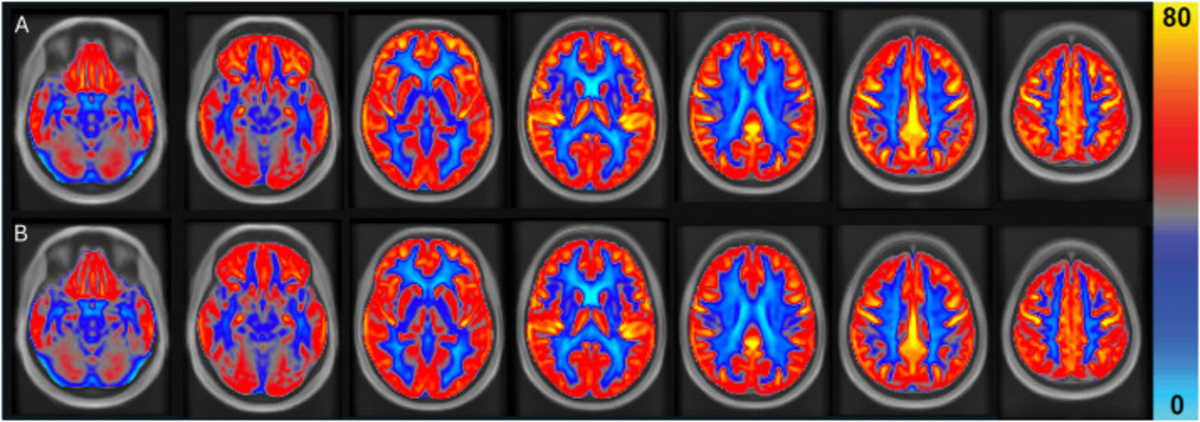

-2

Цвета на снимках отражают уровень кровотока: чем ярче оттенок, тем больше крови поступает к мозговой ткани. Исследователи наложили снимки всех 31 участника друг на друга и привели их к единому стандарту, принятому в нейровизуализации, чтобы сравнение было максимально точным.

После 16 недель с арахисом общий кровоток в мозге вырос в среднем на 3,6 %. Серое вещество получало на 4,5 % больше крови. Особенно заметны были сдвиги в лобных и височных долях — на 6,6 и 4,9 % соответственно. Эти области отвечают за память, речь и сложные когнитивные задачи.